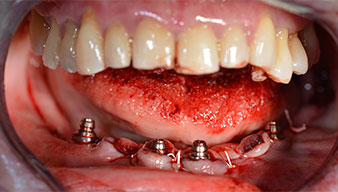

Para compensar la divergencia de los implantes distales, se atornillaron pilares acodados (35 grados) de forma que los perfiles de emergencia de todos los implantes quedaran en la posición más vertical posible en relación con la mordida. Este paso es necesario para poder atornillar de forma oclusal el tratamiento provisional y, posteriormente, el definitivo (figs. 15 y 16).

Tras esto, se realizan la impresión y el registro de la mordida para que el protésico dental pueda empezar inmediatamente con la elaboración de la prótesis provisional, cuya implantación se realiza el mismo día (figs. 17 y 18).